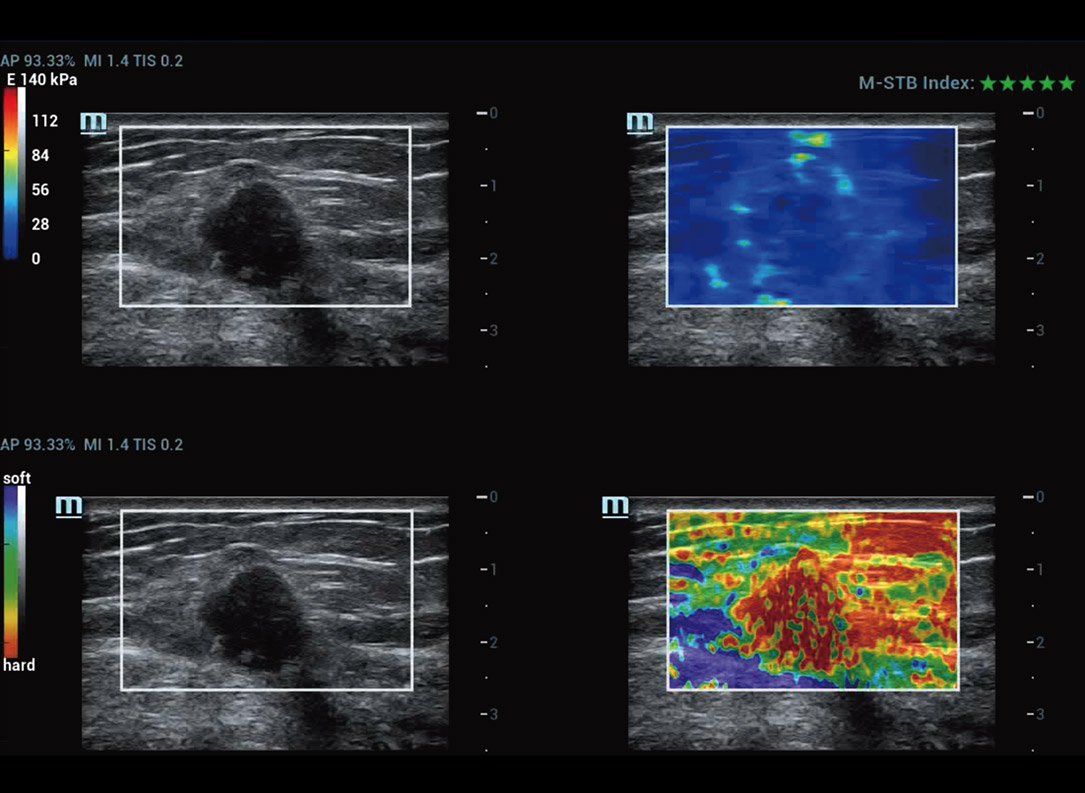

M-Reference Multi-parametrische analysetools

M-Ref. C&E

M-Ref. C&E Borst kwaadaardig

M-Ref. C&E ondersteunt het weergeven van het contrast en de STE in ├®├®n vlak voor vergelijkende beoordeling van perfusie en elasticiteit.

M-Ref. E Compare

M-Ref. E Compare Borst kwaadaardig

M-Ref. E Compare ondersteunt het weergeven van zowel de realtime strain-elastografie als STE in ├®├®n vlak voor de evaluatie van weefselstijfheid.